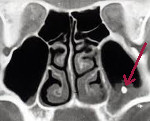

КТ пазух. В полости левого верхнечелюстного синуса плотное инородное тело (пломбировочный материал выходит из корня зуба).

• Радиационные исследования. При рентгенографии и компьютерной томографии околоносовых пазух обнаруживаются нарушение пневматизации, потемнение синусов, утолщение слизистой оболочки, уровень жидкости и наличие инородного тела. Для лучшей наглядности эти исследования проводятся с контрастом. В этом случае инородное тело выглядит как дефект наполнения пазухи. Экосинусоскопия (УЗИ околоносовых пазух) может обнаружить инородные тела, отрицательные для рентгеновских лучей.